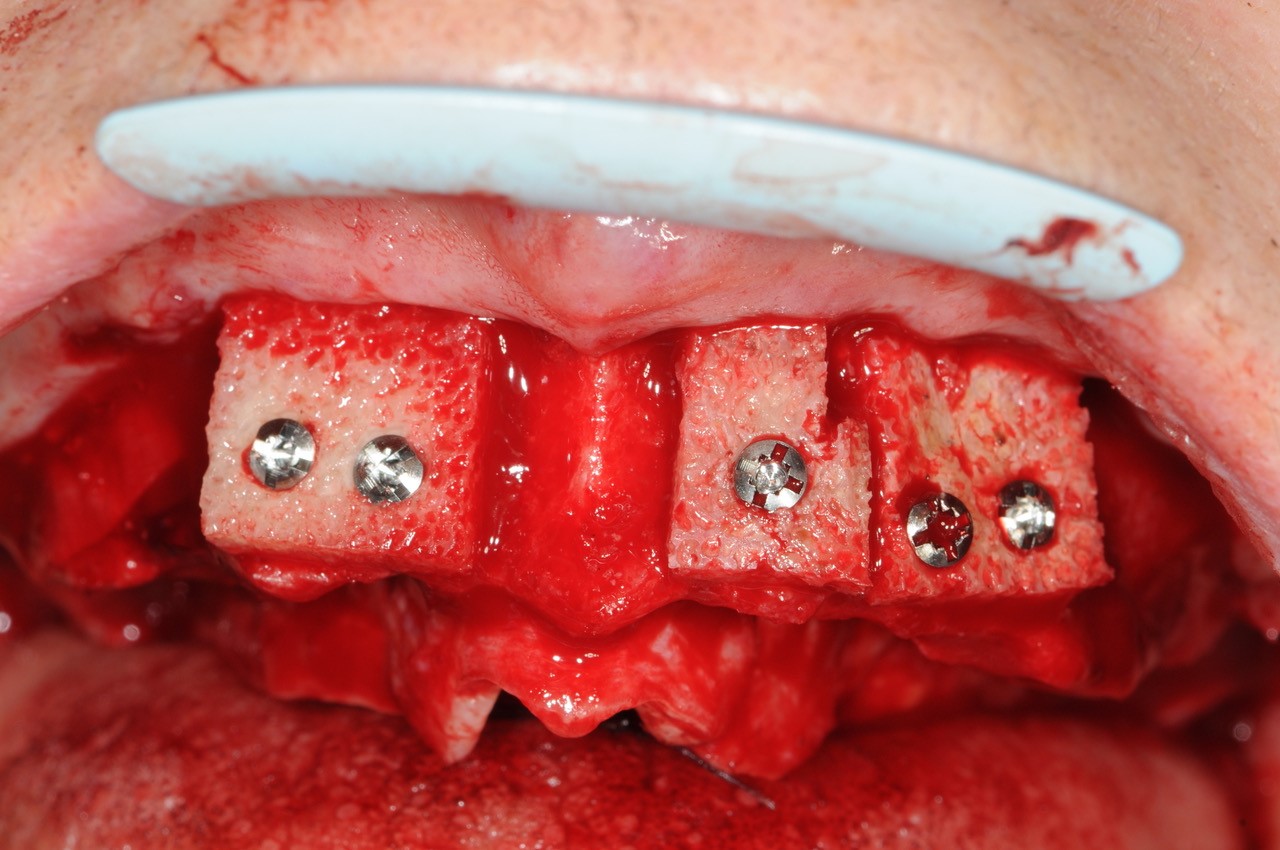

09/21 - Fixation of multiple blocks with osteosynthesis screws

Reconstruction of maxillary ridge with maxgraft® block - Amit Patel

10/21 - Fixation of multiple blocks with screws / crestal view